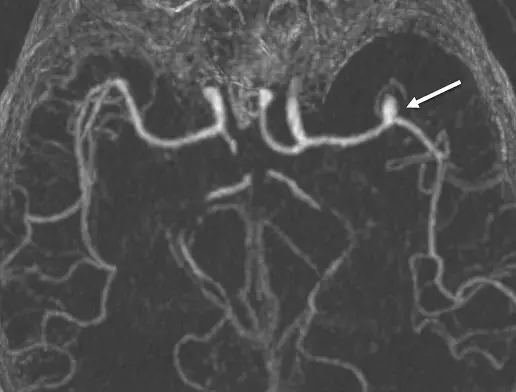

- 影像模式:這是一張頭部電腦斷層血管攝影(CTA)影像。

- 後處理技術:影像呈現極高對比的血管樹狀結構,而周圍的腦實質背景被抑制,這是典型的**最大強度投影(Maximum Intensity Projection, MIP)**技術。MIP 會將投影路徑上具最大 CT 值(即充滿含碘對比劑的血管)的體素(Voxel)顯示在二維畫面上,是臨床上評估腦血管病變的標準後處理流程。

- 解剖構造與病灶:從血管分佈來看,此為軸切面(Axial view)或略帶角度的冠狀切面。影像中央可見兩側內頸動脈(ICA)向上延伸後,向內前側分出大腦前動脈(ACA),並在中線由前交通枝動脈(Acom)相連。同時,向兩側水平、外側延伸的則是大腦中動脈(MCA)。

- 箭頭所指處:白色箭頭指向左側(影像右側,符合放射學常規)向外延伸的大腦中動脈(MCA)分叉處,該處有一個明顯的囊狀突起物,這是典型的**大腦中動脈